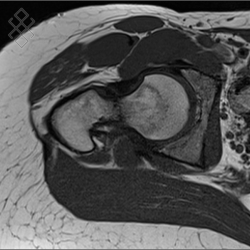

IRM de la Hanche